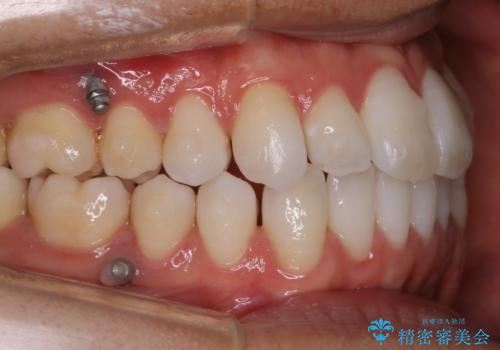

- 矯正装置

- マウスピース(インビザライン)

- 88万円+TAX(マイクロインプラント費用込み)費用は治療当時の料金となります

非抜歯での治療

抜歯をせずに歯のガタつきを治すためのスペースを作るために

①歯の遠心移動

②歯列弓の拡大

③IPR(歯を少し小さく削る)

この3つの方法を複合的に組み合わせて治療を行いました。